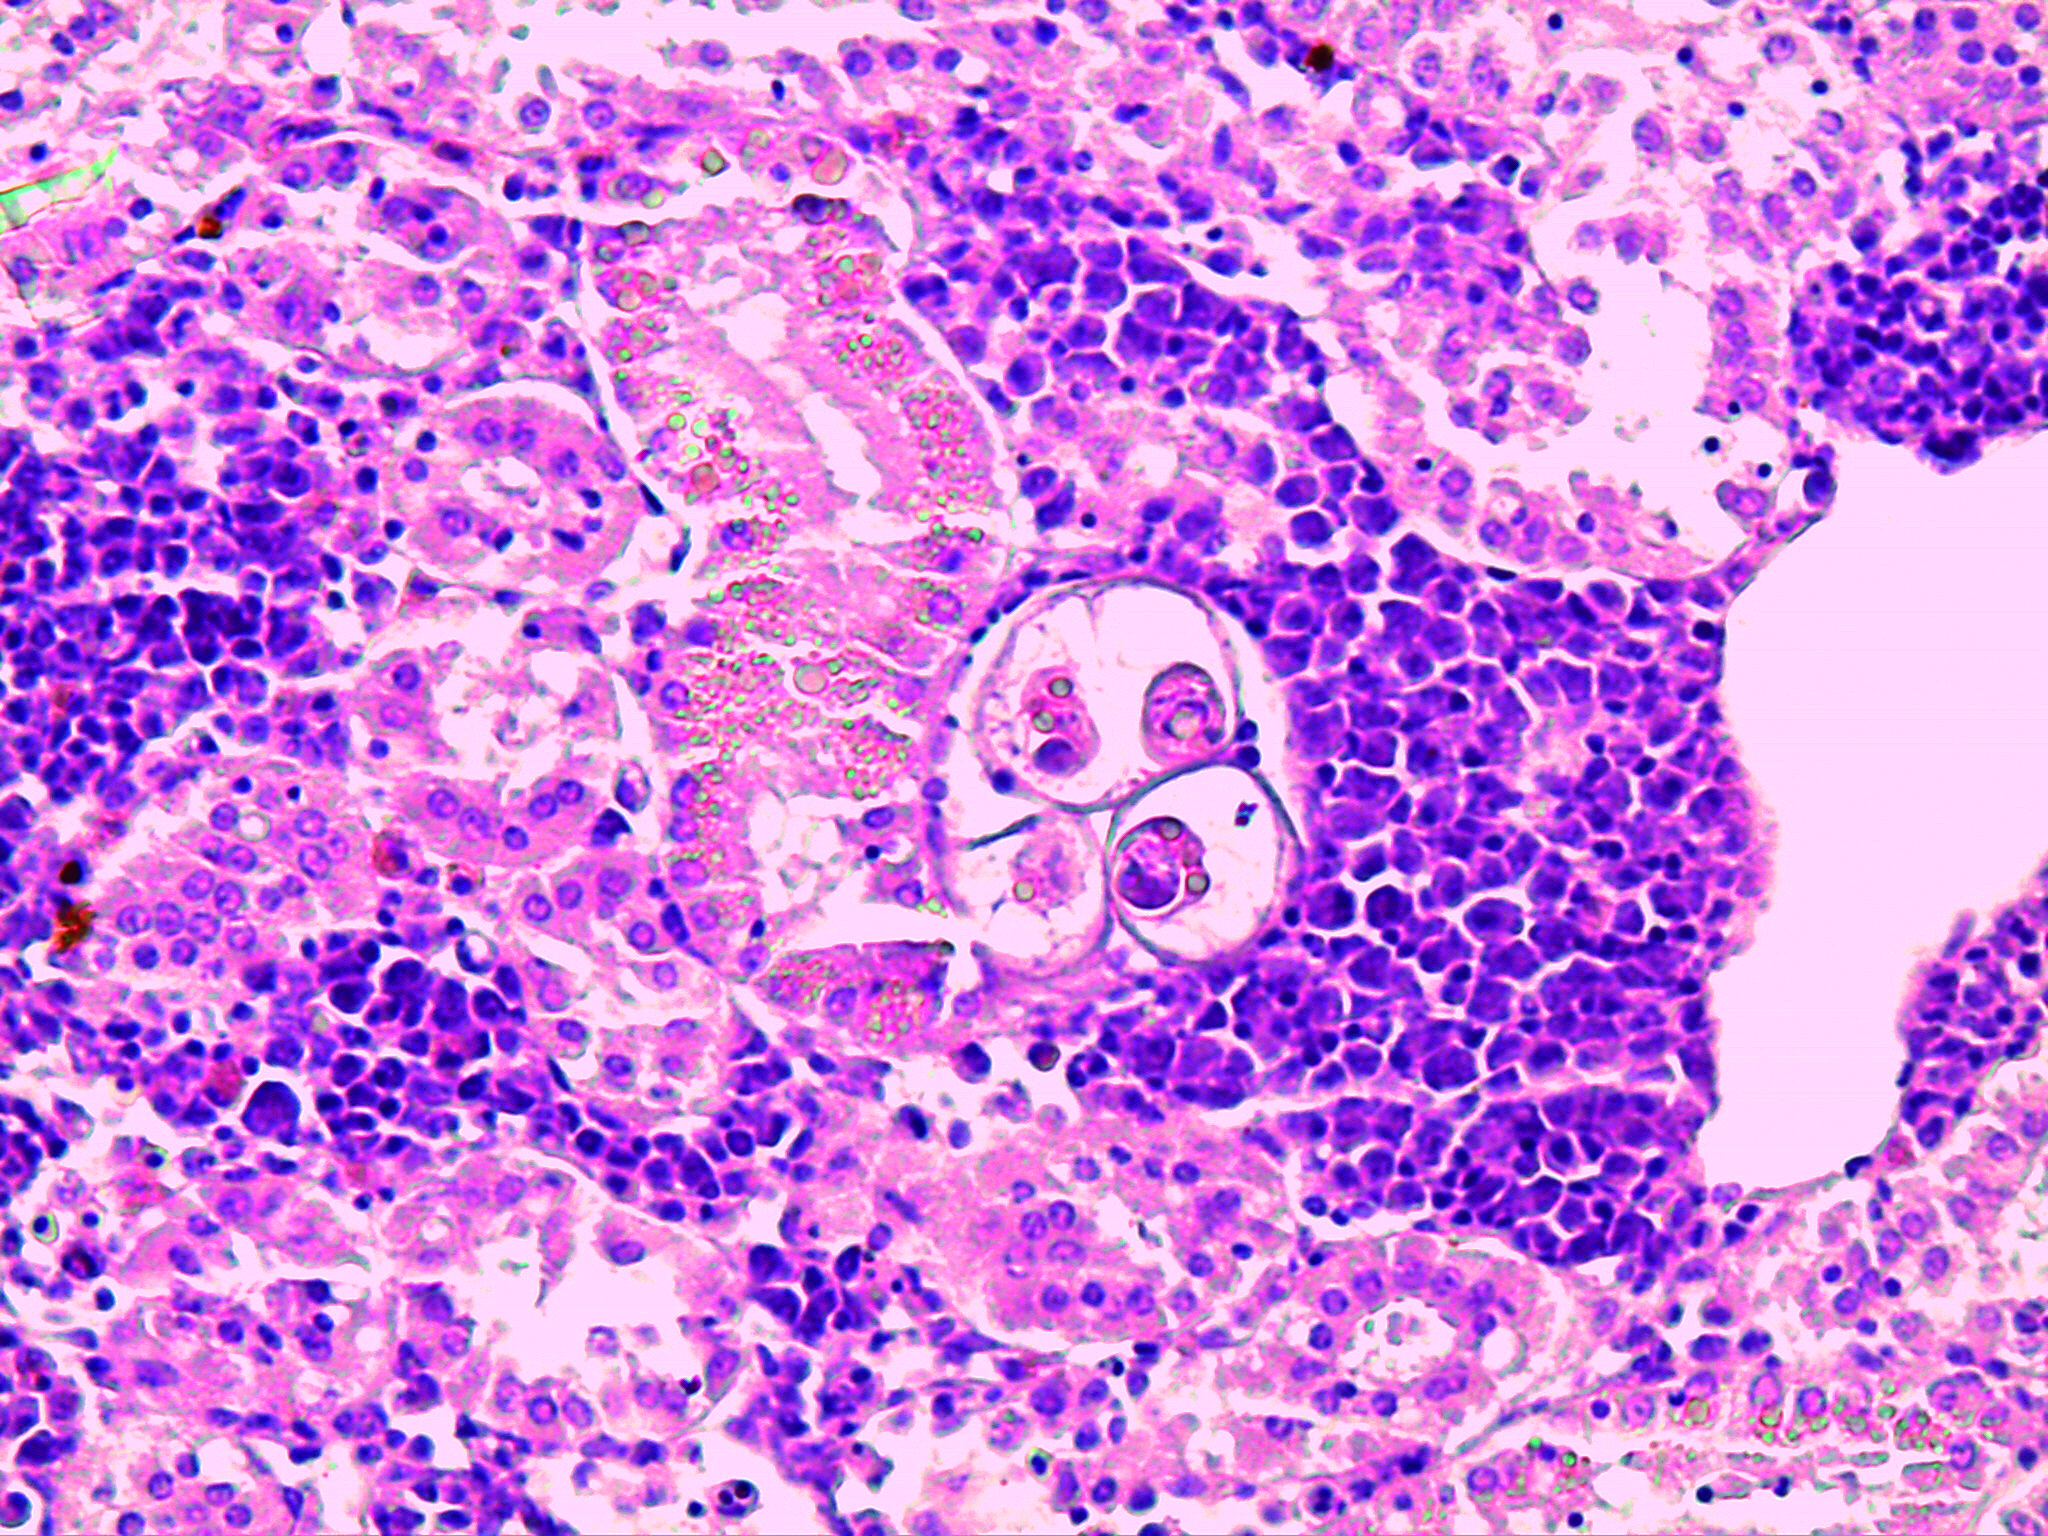

Microsporidiosi digestiva

Agente: Enterospora nucleophila (Enterocytozoonidae, parassita Microsporodiano).

Sintomi: Il protozoo intranucleare risiede all'interno dei nuclei degli enterociti e delle cellule rodlet nel tratto digestivo dell'orata. I pesci colpiti mostrano deperimento e grave anemia.

Appare durante l'inverno, ma la malattia può diventare più grave quando le temperature aumentano.

Controllo: Nessun trattamento. La prevenzione consiste nella separazione di pesci di diverse dimensioni per ridurre la trasmissione.